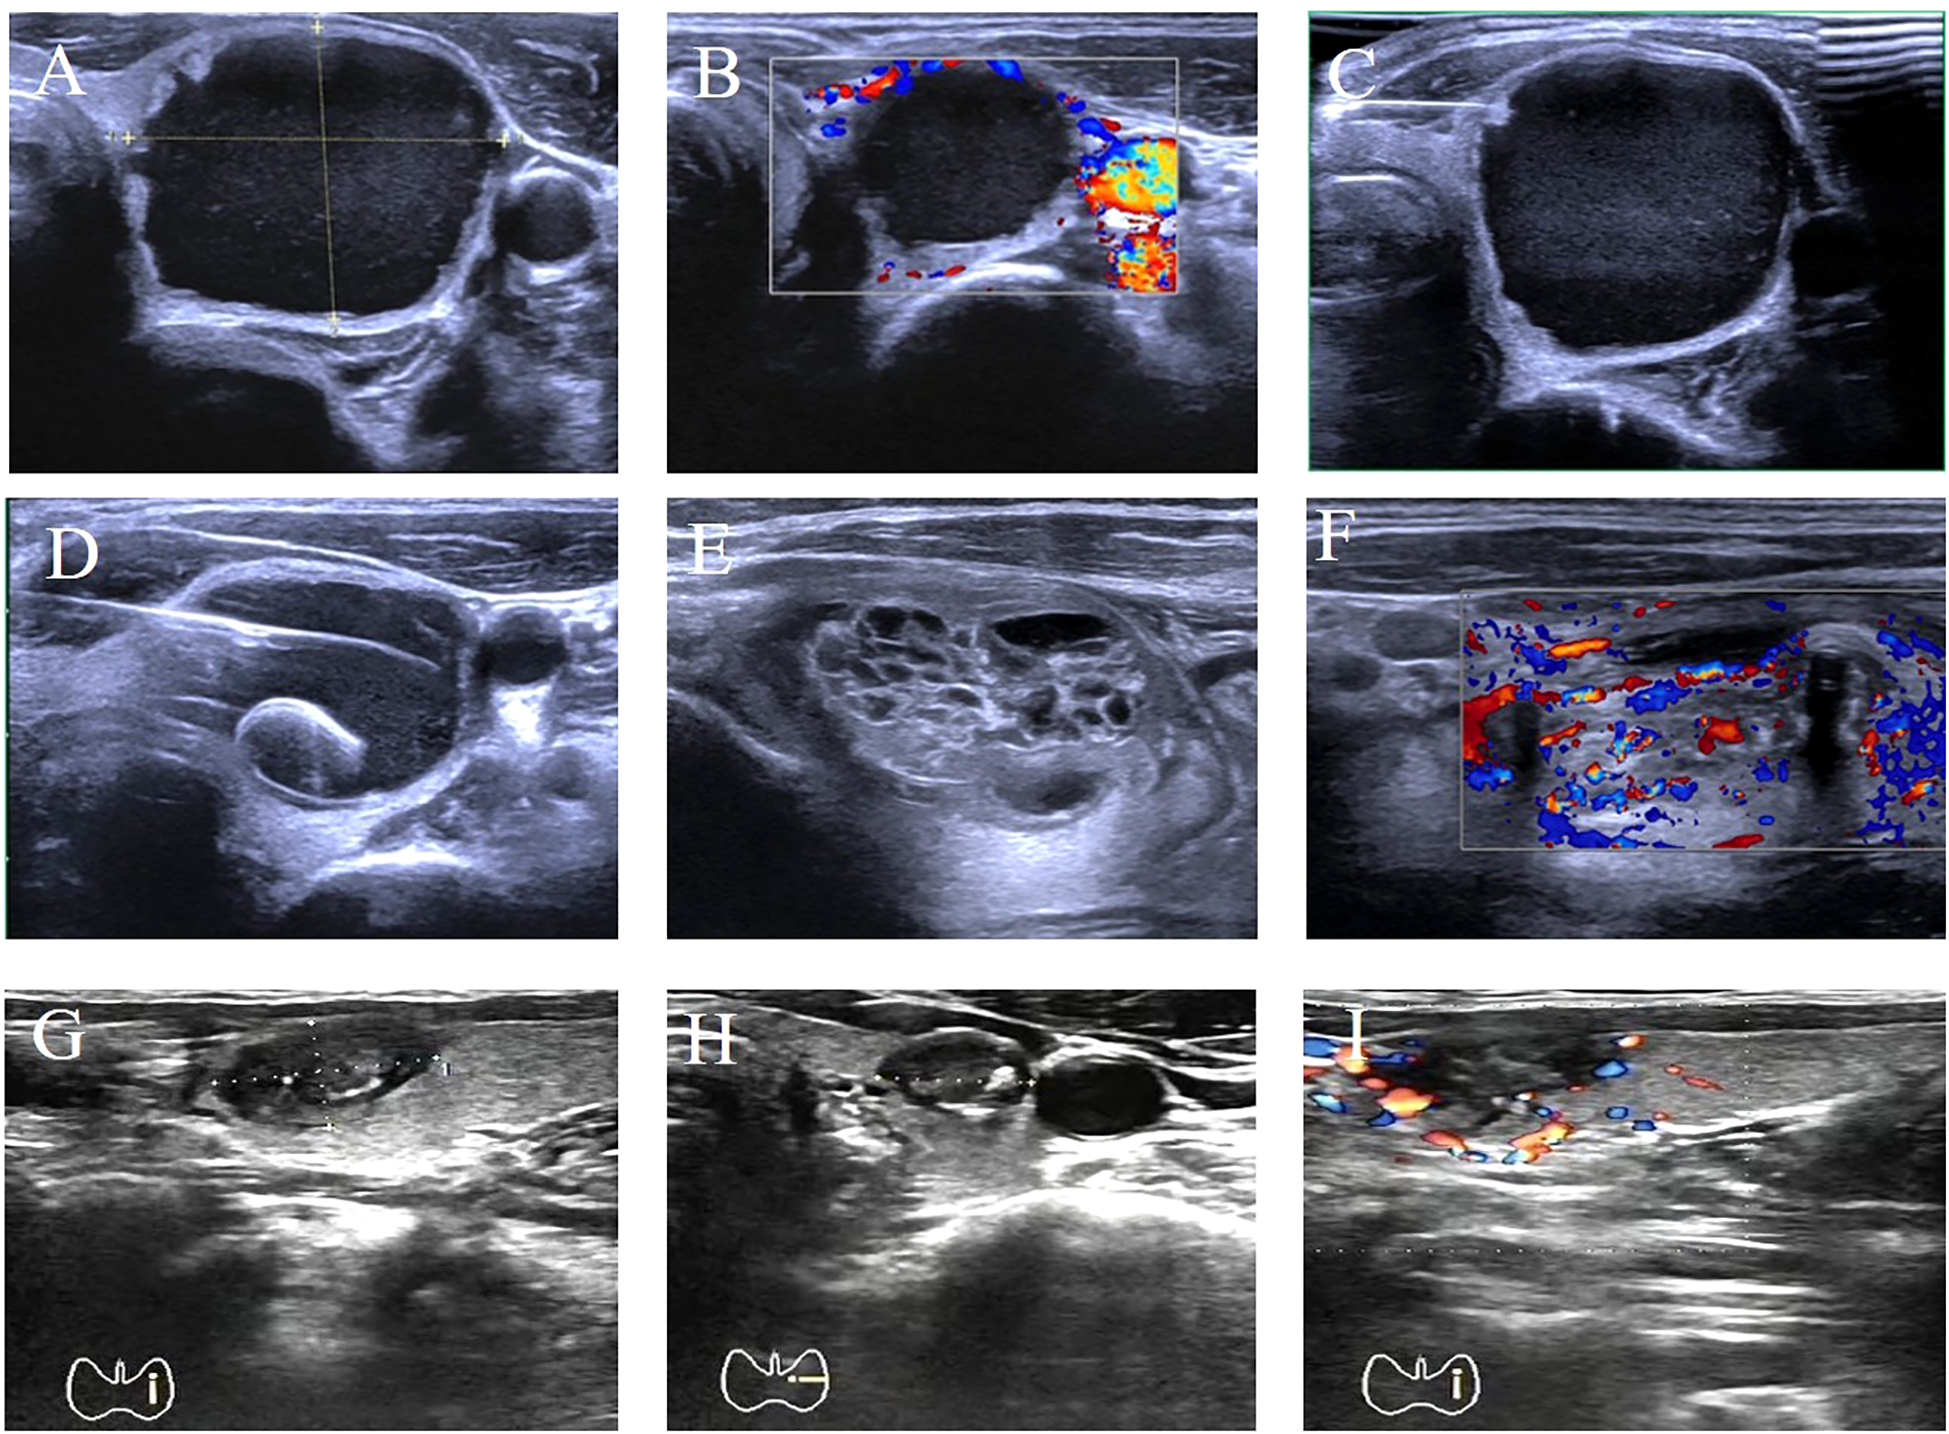

Using the volume reduction rate (VRR) of the ablation zone as the efficacy evaluation metric for thermal ablation therapy, both groups exhibited significantly decreased tumor volumes at 3 and 6 months postoperatively compared to preoperative baselines (P<0.05). The cervical catheter ablation group demonstrated a significantly higher VRR than the non-catheter ablation group, with statistical intergroup difference (P<0.05). See Table 3. The ultrasound images of one patient before catheter drainage, after catheter drainage, after radiofrequency ablation, and during the follow-up period are shown in Figure 2, which shows that the treatment effect is very significant.

Figure 2

Comparison of preoperative and postoperative results in one patient. (A) Transverse plane ultrasound showing a 35×30×23 mm cystic-solid mass (predominantly cystic) in the left thyroid lobe. (B) Color Doppler ultrasound demonstrating blood flow signals around the lower pole of the nodule. (C) Longitudinal plane ultrasound during fine-needle aspiration biopsy (FNA) of the nodule. (D) Transverse plane ultrasound showing placement of a single-lumen pigtail catheter into the nodule. (E, F) Longitudinal plane ultrasounds on postoperative day 2 revealing full expansion of the solid component, thickened cyst wall, and appearance of blood flow signals. (G–I) Transverse plane ultrasound images at different levels obtained 3 months post-ablation. Ultrasound Imaging Planes: (A) Transverse; (B) Color Doppler; (C) Longitudinal (FNA); (D) Transverse (catheter placement); (E, F) Longitudinal; (G–I) Transverse (post-ablation). Post-ablation nodule size: 13.6×8.6×9 mm. Volume Reduction Rate (VRR): 95.8%.